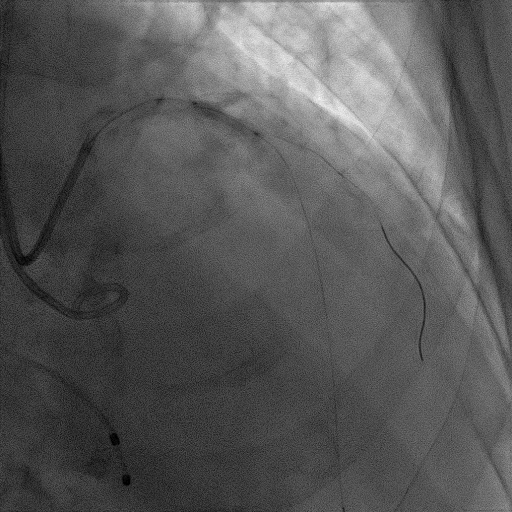

CAG:LAD近中段弥漫钙化,近段80%狭窄,中段90%狭窄,D190%狭窄,中间支近段90%狭窄,右冠近中段弥漫病变,最重狭窄50%。考虑患者胸痛症状可能为冠心病+AS共同作用,以及患者冠脉病变钙化严重,予以旋磨+PCI+TAVR一站式处理。

于中间支植入2.5*18mm支架

1.5mm旋磨头以16万RPM旋磨三次

3.0*15mm球囊后扩张

3.0*15mm球囊预处理LAD近段病变

复查冠脉造影结果满意

造影提示微少量返流,压力监测提示主动脉瓣压差7mmHg